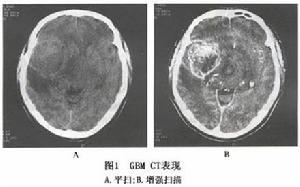

2.CT掃描 腫瘤呈邊界不清的混合密度病灶,其中多有瘤內出血所致高密度表現但鈣化者較少 瘤內壞死及囊性變呈低密度影,而使其形態呈多形性,病灶周圍多數腦水腫較重, 腫瘤與腦組織無明顯邊界。腦室常被壓迫變小,變形或封閉,中線結構常向對側移位。增強後95%的腫瘤呈不均勻強化 常表現為中央低密度的壞死或囊變區 周邊增生血管區不規則的環形、島形或螺鏇形強化影(圖1)。壞死區常位於腫瘤實質內,呈邊界不整齊的低密度區。